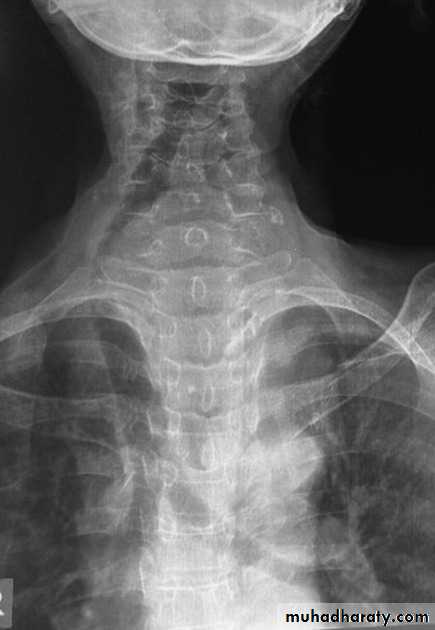

Radiographic featuresChest radiograph

It may show a superior mediastinal radio-opacity causing the deviation of trachea to opposite site. The superior margin of the radio-opacity/mass is untraceable (cervicothoracic sign).

Retro sternal goiter